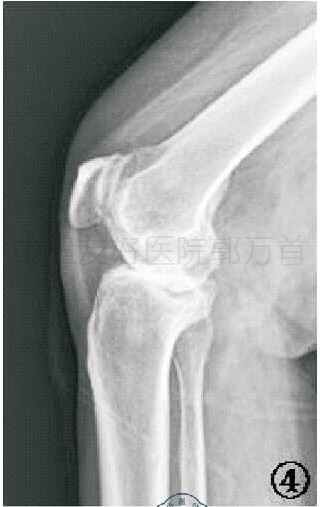

X线片三:外翻应力

外翻应力X线可用来辅助评价外侧间室关节软骨厚度是否正常及内侧副韧带功能是否完整:①如果外侧间室关节间隙变窄提示外侧间室软骨磨损(约<5 mm),这是单髁关节置换的禁忌证。②如果内侧间室关节间隙分离大于等于5 mm,说明内侧副韧带没有短缩,即内翻可

充分矫正,如果外翻应力X线下内翻畸形不能有效矫正,内侧间室关节间隙仍然狭窄,说明内侧副韧带短缩,则单髁关节置换手术不适合。③如果外翻应力X线可以完全矫正内翻畸形及半脱位,可以选择单髁关节置换术。否则,不适合行单髁关节置。